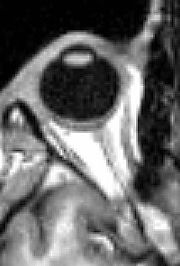

| Human Eye Anterior Segment - Magnified view seen on examination with a slit lamp under diffuse illumination showing conjunctiva overlying the white sclera, transparent cornea, pharmacologically dilated pupil and cataract | |